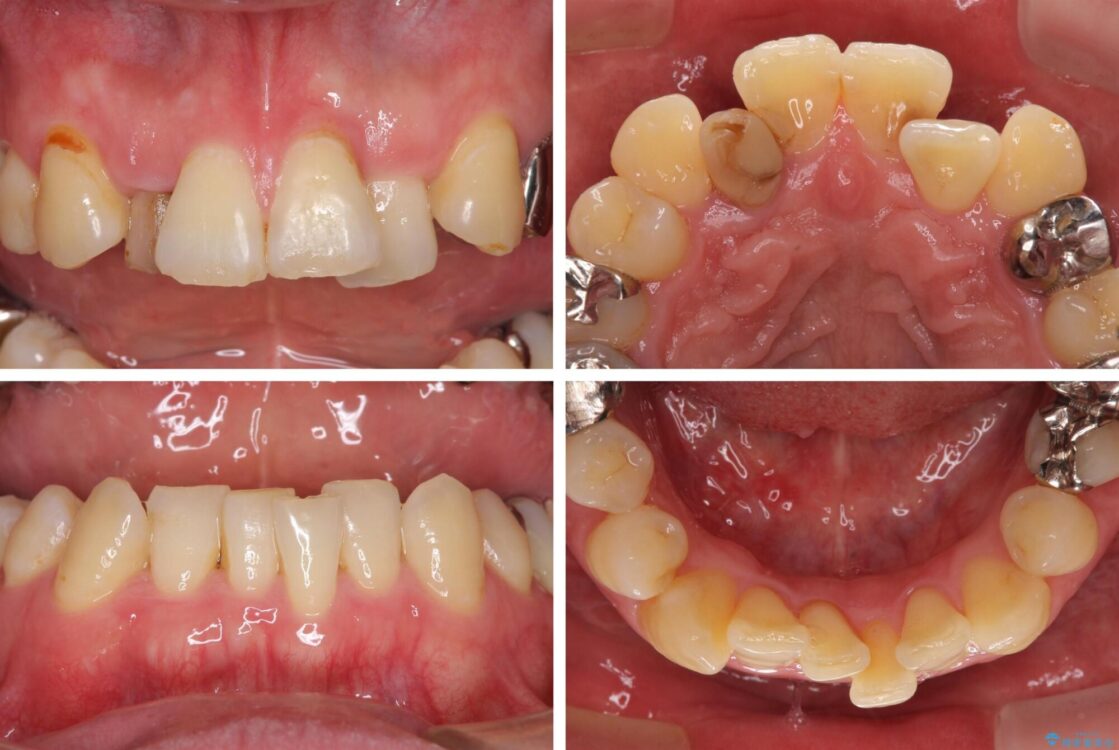

奥歯の痛みと前歯のデコボコを気にして来院された患者様です。

咬み合わせは受け口傾向であり、上顎前歯の叢生が顕著であったことから、第1小臼歯抜歯による矯正治療も検討しましたが、下顎大臼歯を左右ともに抜歯するため、非抜歯による矯正治療を行うこととしました。

治療前

• 割れてしまった奥歯とデコボコの前歯 矯正治療とインプラント治療 治療前画像